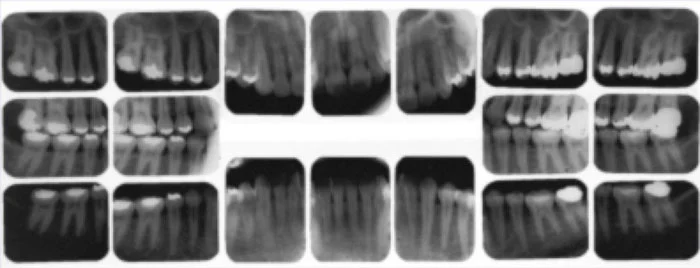

Complete series x-ray.